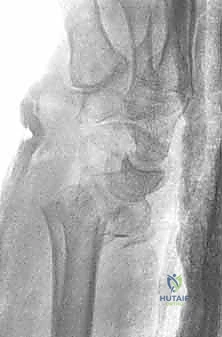

صورة طبية توضح كسر الناتئ الإبري

صورة لكسر في رأس الزند

توضيح لكسور الجزء الكردوسي الكردوسي

استخدام الأشعة السينية في التشخيص

1. الأشعة السينية (X-rays): بوضعيات متعددة (أمامية خلفية، وجانبية دقيقة). الوضعية الجانبية الحقيقية (True Lateral) حاسمة لاكتشاف أي خلع جزئي في المفصل (DRUJ).

2. الأشعة المقطعية ثلاثية الأبعاد (3D CT Scan): تُستخدم في الكسور المفتتة أو كسور رأس الزند المفصلية المعقدة، حيث تعطي خريطة دقيقة للجراح قبل الدخول لغرفة العمليات.